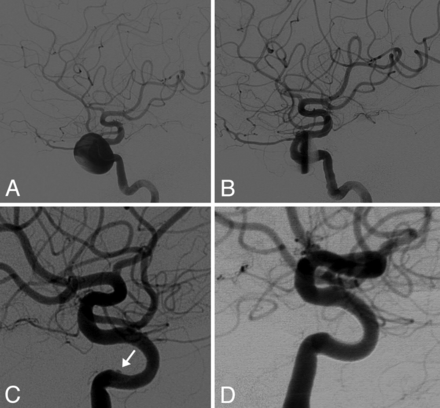

Adequate angiographic and clinical follow-up was available in 36 patients, and their angiographic and clinical outcomes are demonstrated in On-line Table 2. One patient was excluded from occlusion analysis due to subsequent transvenous coiling of the cavernous sinus for treatment of a carotid cavernous fistula. At final angiographic follow-up (3–36 months; mean, 10.9 months), 71% (25/35) had complete occlusion, and of the 10 patients with incomplete occlusion, 40% (4/10) had minimal remnants present on angiography. In patients who had incomplete occlusion noted on 6-month angiograms and also had a follow-up angiogram at 12 months or later, 50% (4/8) were found to have progressed to complete occlusion at final follow-up (Fig 1).

A, Lateral digital subtraction angiography of the left ICA in a 67-year-old woman demonstrates a large (20 mm) aneurysm originating from the cavernous segment of the ICA. B, Immediate postplacement image of 3 PEDs demonstrates stasis of contrast within the aneurysm. C, Follow-up lateral DSA at 6 months demonstrates a minimal remnant (white arrow). D, Final angiographic follow-up demonstrates complete aneurysm occlusion at 36 months.